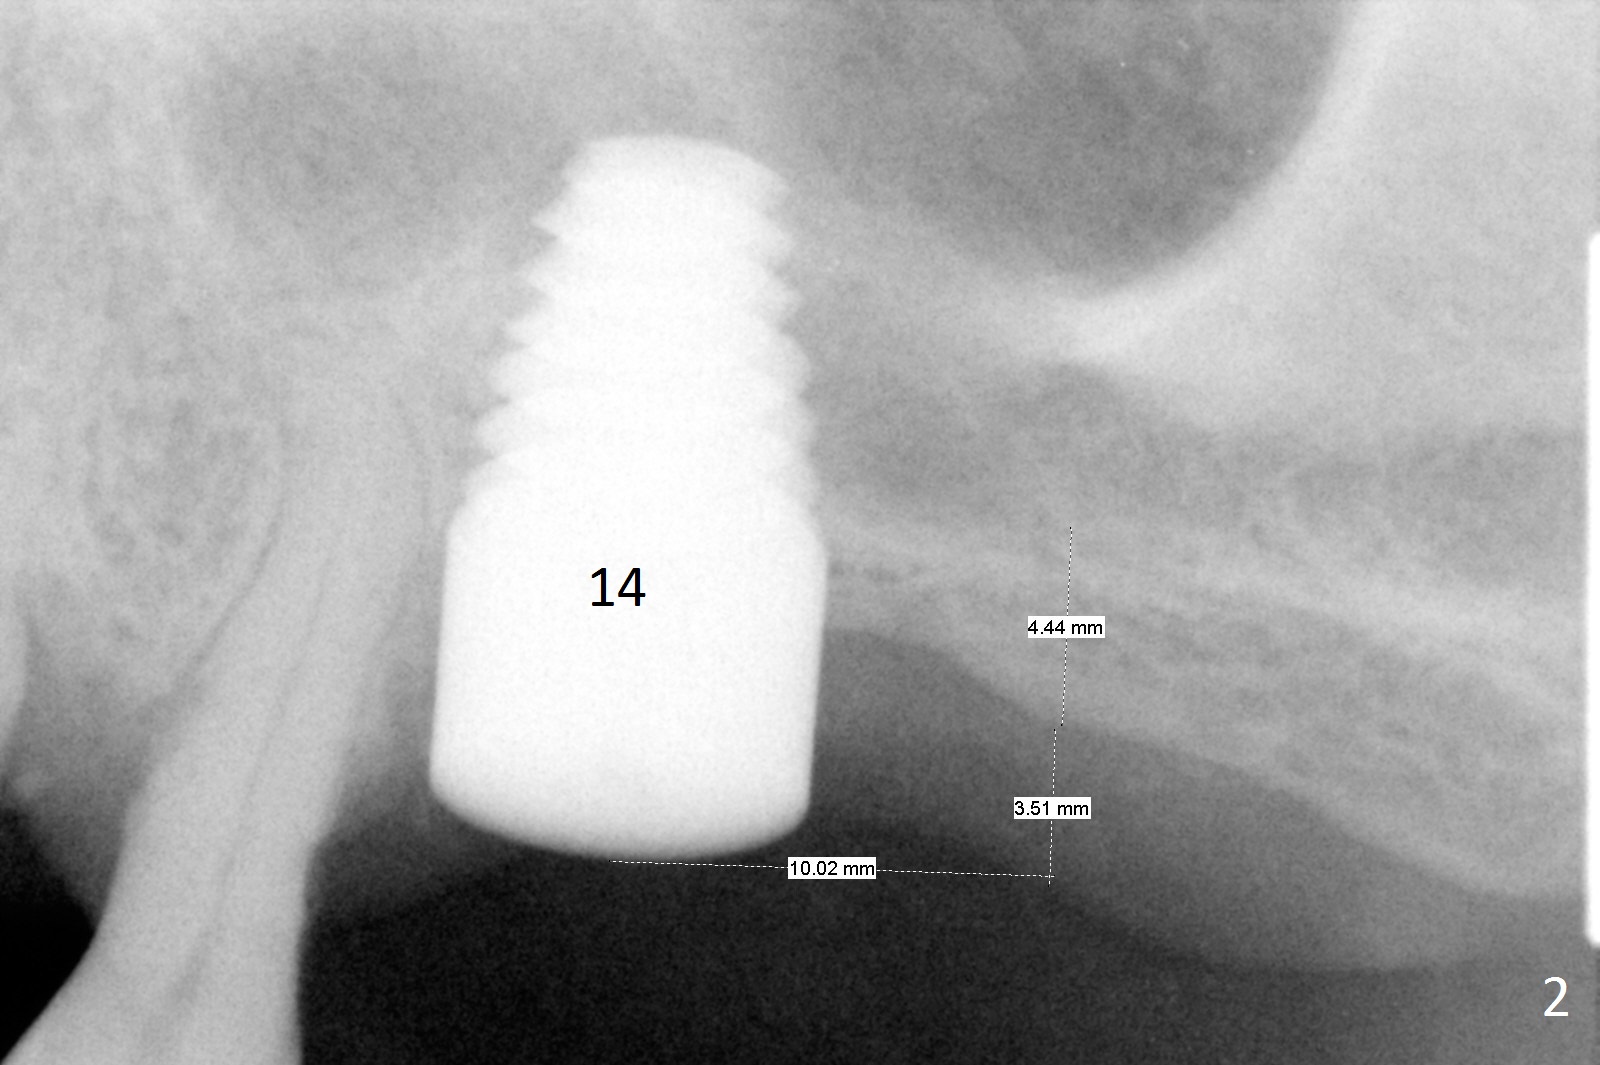

A 58-year-old man has two types of implant complications: periimplantitis at #4 (in spite of 2 bone graft surgeries, Fig.1) and abutment loosening at #14 and repeatedly 19 (probably due to bruxism, Fig.2,3).

To overcome bruxism, implants will be placed at the 2nd molar sites (total 4). Since the implant at #19 was placed distal, the crowns at #18 and 19 will be splinted. The unipost at #14 is 6 mm, 10º cemented with Ketac (implant 8x14 mm). To increase retention, use bonding and place 1 or 2 heavy retention grooves or use a straight abutment. If the existing abutment cannot be removed, enlarge the retention groove and bury a piece of wire in the groove with bonding. The last resort will be splinting with #15.